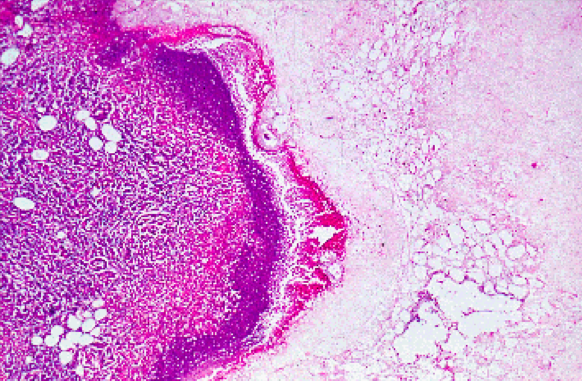

What type of gastric carcinoma will commonly be missed on upper GI endoscopy?

Linitis plastica caused by signet-ring cells (shown below). This type of tumor is rare, most gastric tumors are exophytic or flat.